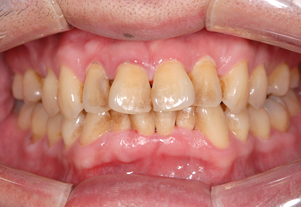

歯周病治療

しっかりと治療を行い、

健全な歯肉を取り戻しましょう。

歯周病は進行すればするほど治療が難しく費用もかかってしまいます。もちろん歯周病にならないように日々のケアをすることはとても大切ですが、万が一歯周病が進行してしまった際も、できる限り早めの処置で歯を抜かなくて済む場合もございます。

まずは当院にご相談ください。

症例2(歯肉移植)

Before

After

- POINT

- 右上2番(赤丸の箇所)の歯茎が下がってしまった患者様です。

歯茎が薄く歯もしみてしまい歯磨きしにくいため、上あごから歯肉を移植しました。

厚みのある歯茎になり、しみる症状も改善されました。